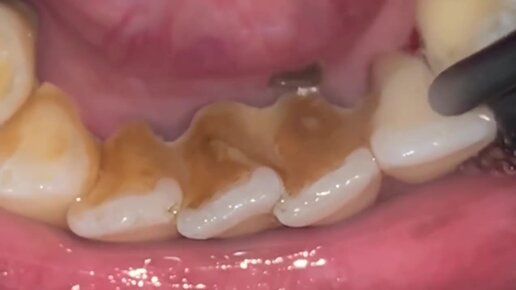

Как удаляют зубной камень?